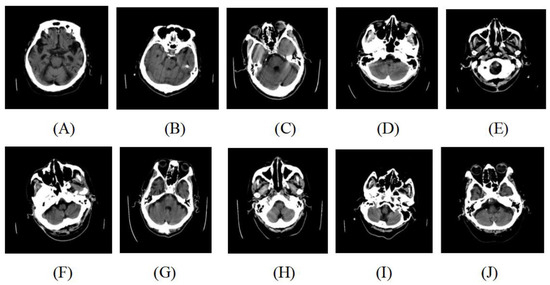

| Slice ID | Region Label | Quality Label |

|---|---|---|

| a | 1 | 0 |

| b | 2 | 1 |

| c | 1 | 0 |

| d | 3 | 1 |

| e | 2 | 1 |

| f | 1 | 0 |